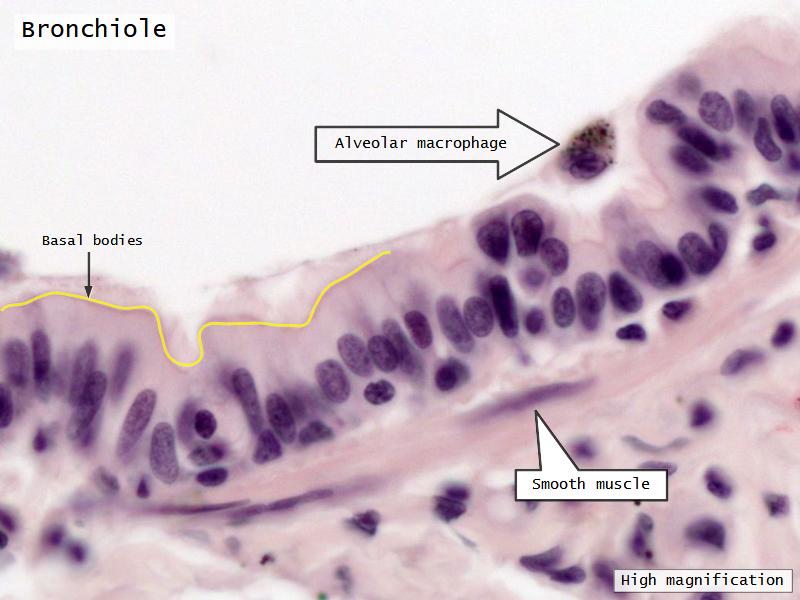

Bronchi - Transitions

- Intrapulmonary bronchi

- Irregular cartilage

- Respiratory epithelium

- Glands

- Bronchioles

- Smooth muscle REPLACE cartilage

- Ciliated columnar > Ciliated cuboidal

- NO glands - goblet cells -> secretory cells

- Terminal bronchioles

- Smooth muscle

- Ciliated cuboidal epithelium

- Secretory cells